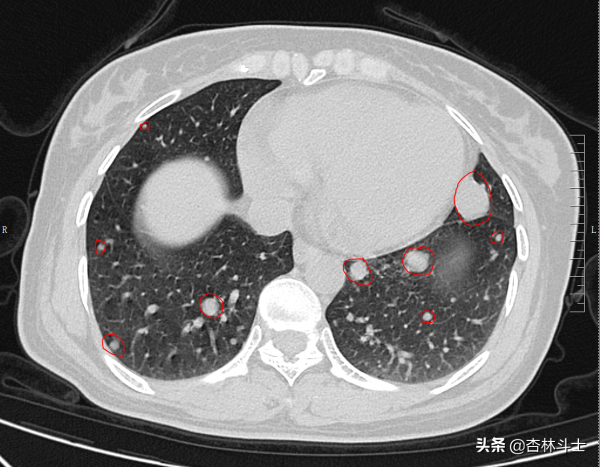

磁共振表現並結合患者病史體徵,考慮患者左側大腿上部巨大腫塊為惡性軟組織肉瘤,遂安排了頭顱3T磁共振增強及胸部CT平掃、腹部CT平掃+增強。結果胸部CT平掃部分影象如下:

圖中紅圈內為大小不等軟組織腫塊,結合既往檢查,考慮腫瘤血行播散至肺部,導致肺內多發轉移瘤。